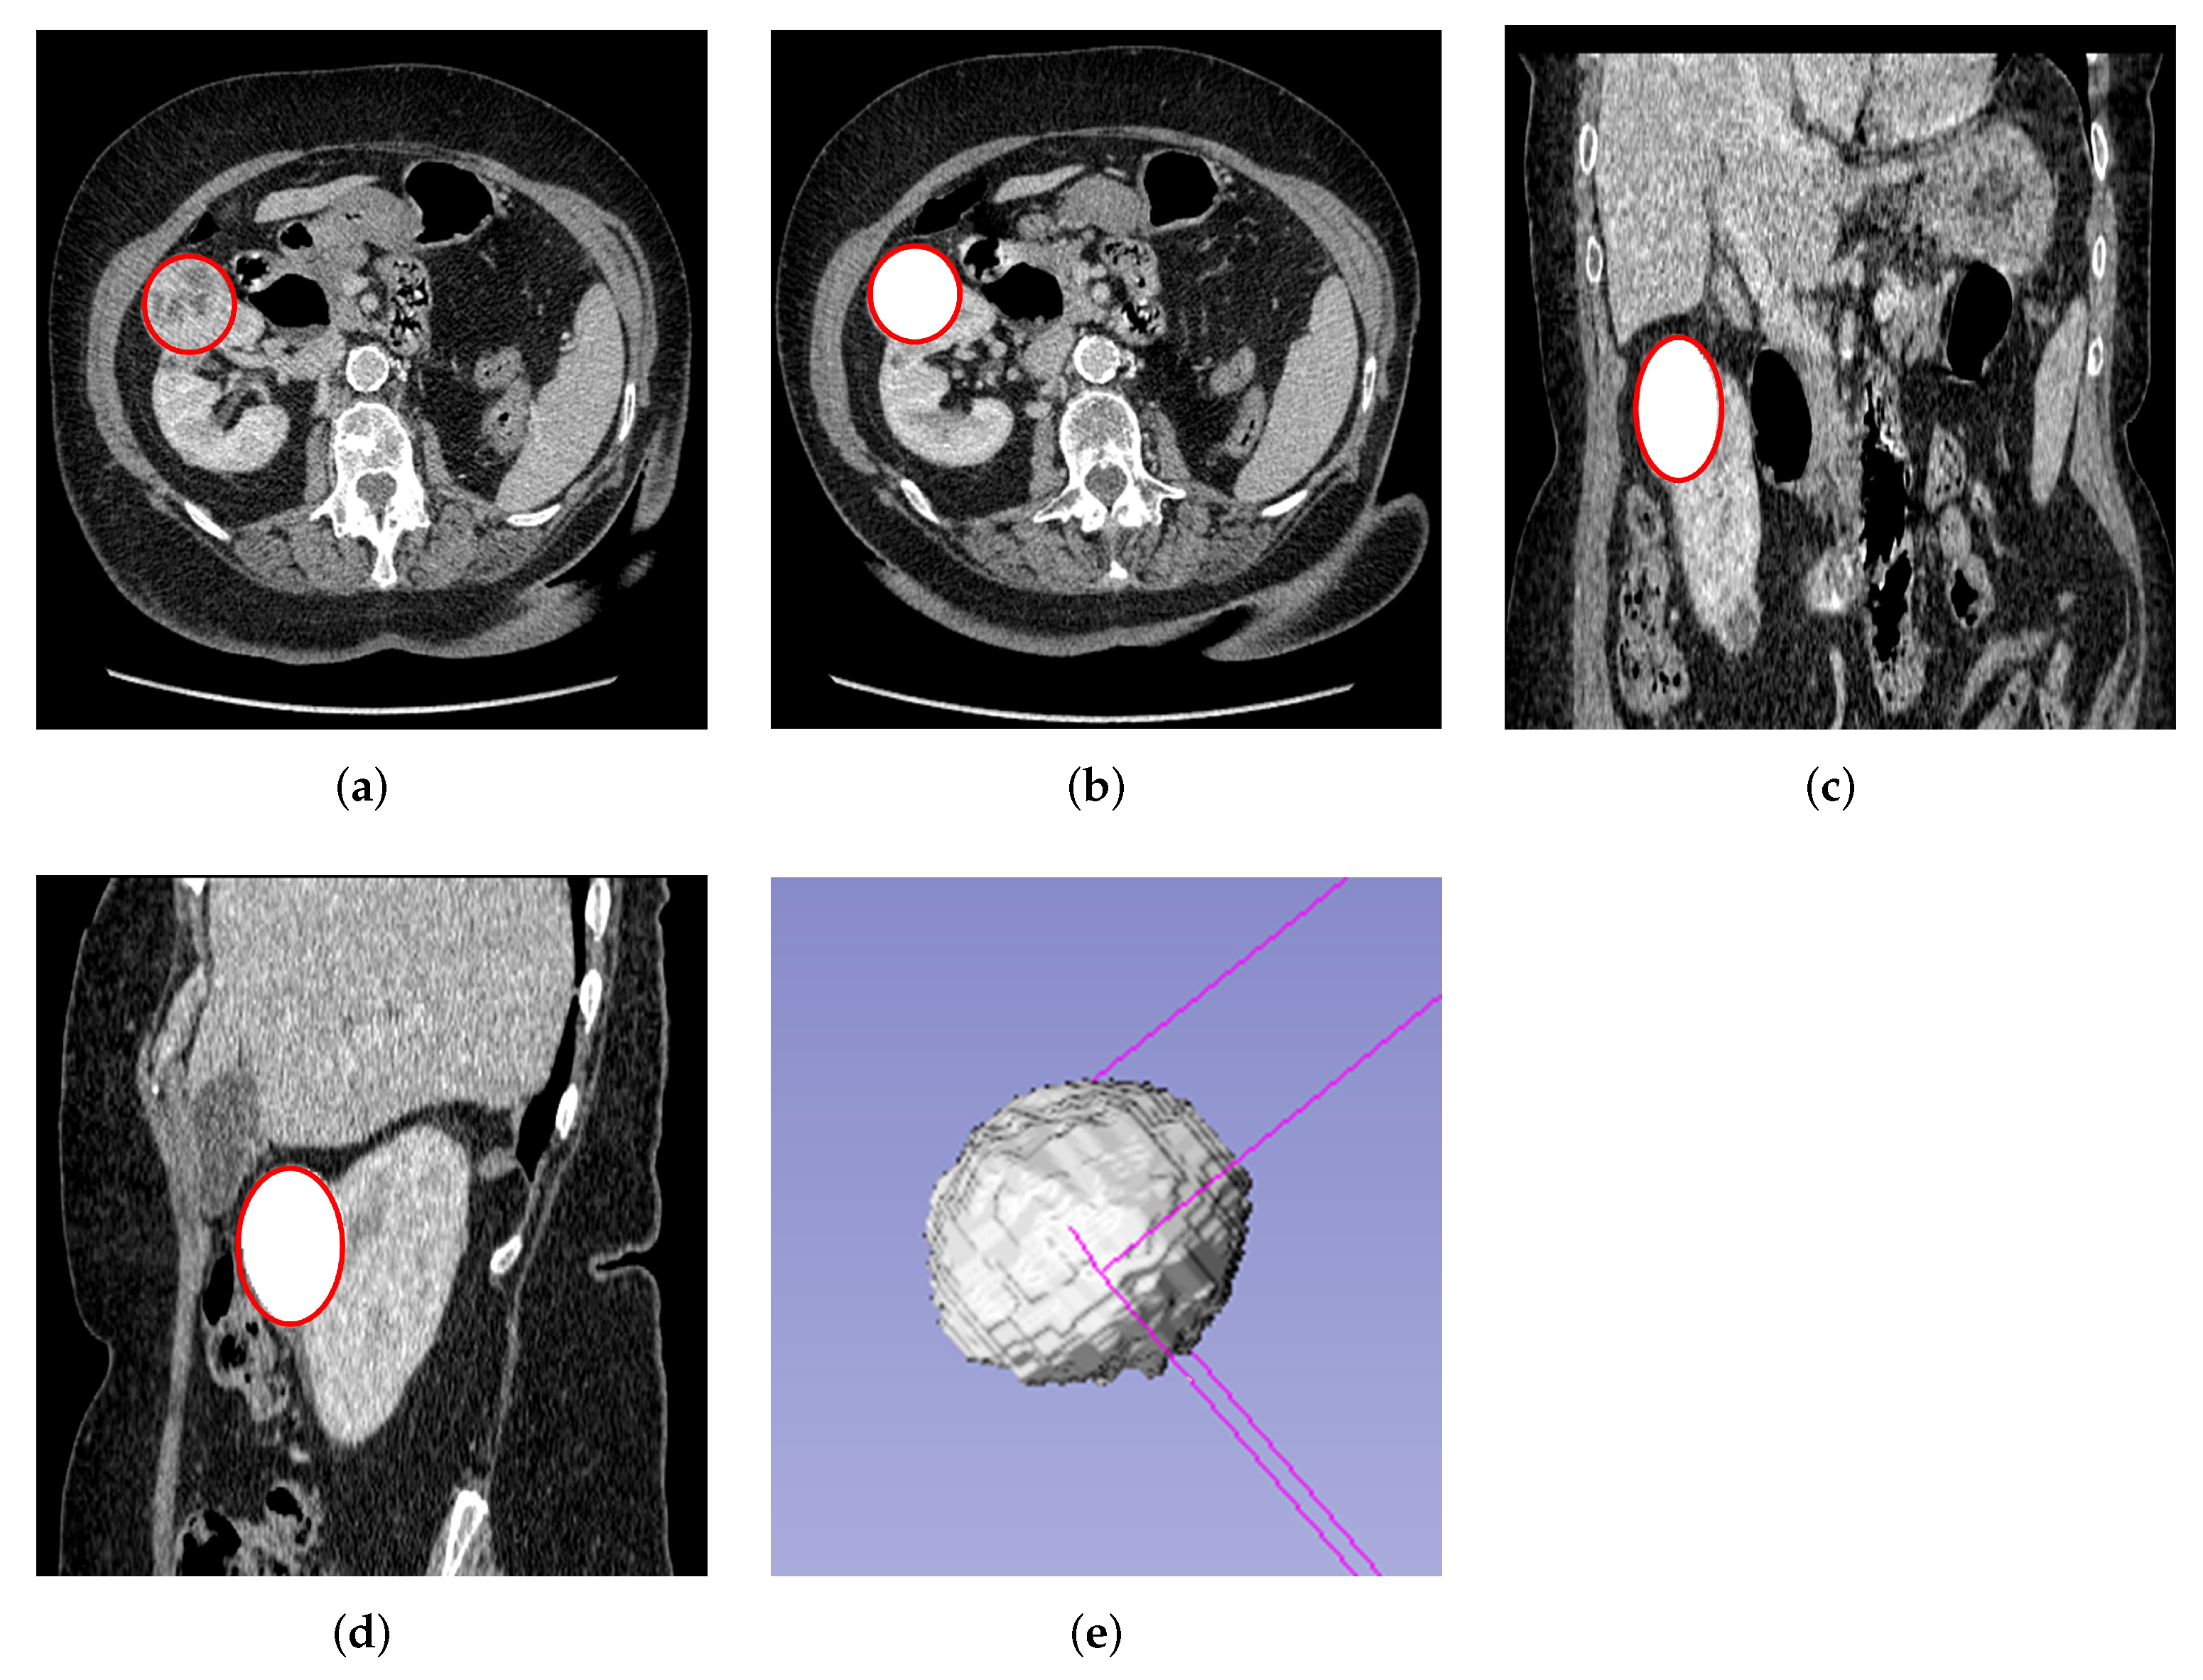

Finally, 3D volume of interest (VOI) segmentation was done semi-automatically using the Slicer 3D software version 4.11, where the VOI was automatically generated after segmenting the first few slices. The 3D segmentation was done as shown in Figure 2. Both 2D and 3D segmentations were performed by a blinded experienced investigator (A.A) delineating the ROI about the edges of the tumors without prior knowledge of the patient’s condition. After that, the segmented masses were revised and confirmed by an experienced urological surgical oncologist (G.N), who further took into consideration the notes of histology and radiology reports. The study used the histopathological assessment after biopsy or nephrectomy as the gold standard.

Figure 2.

Semi-automatic 3D slice tumor segmentation using the volume editor of the slicer 3D software. (a) Original axial plane of the 3D image with VOI. (b) Segmented axial tumor plane mask from the kidney. (c) Segmented tumor mask of coronal plane. (d) Segmented tumor mask of sagittal plane. (e) 3D segmentation volume mask.